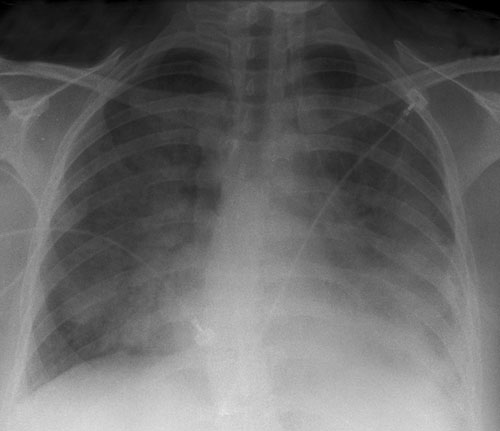

On Day 2, the patient continued to be febrile and two sets of blood cultures were performed. Further tests showed a raised C-reactive protein level (380 mg/L; RI, < 8.0 mg/L) and a mild coagulopathy (international normalised ratio, 1.4; RI, 0.8–1.2) with thrombocytopenia (platelet count, 123 × 109/L; RI, 150–400 × 109/L) suggesting early disseminated intravascular coagulation. That evening, the patient developed respiratory distress and hypoxaemia, with an arterial partial pressure of oxygen of 66 mmHg despite receiving a fraction of inspired oxygen (Fio2) of 80%. She was transferred to the intensive care unit, where she received non-invasive ventilation. A chest x-ray revealed bilateral patchy infiltrates consistent with a pneumonic process (Box 1). Antibiotic treatment with ceftriaxone and azithromycin was initiated.

1 Chest radiograph (mobile, erect) taken on Day 2, showing diffuse bilateral infiltrates consistent with a pneumonic process